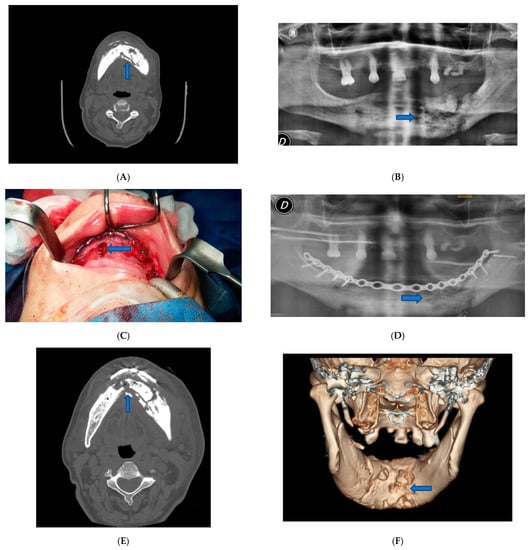

The second case was an 80-years-old woman of Caucasian origin who referred bilateral pain in the mandibular body. The patient was treated with continuous therapy with bisphosphonates.

In this second case, despite the absence of fractures, it was decided to intervene and apply an epi-mucosal fixation because of the very high risk of pathologic fracture due to the osteonecrosis outbreak. Surgery was performed under general anesthesia. After the debridement and removal of the necrotic bone with sequestrectomy and bone trimming, also in this case we proceeded to an epi-mucosal fixation performed using SMART Lock screws and plates without elevating the mucoperiosteal flap (Figure 2C). As in the first case, we proceeded to the preparation of autologous PRF with the application of the PRF directly to the site of intervention. A vicryl polyglactin (91, 3/0) absorbable suture was used to close the flap.

Figure 2.

Patient 2. (A) Pre-operative panoramic X-ray examination showed no fractures, but there was a subversion of the normal organization of the bone. (B) Pre-operative X-Ray image showed lithic area in the lower branch. (C) Epi-mucosal fixation performed using SMART Lock screws and plates without elevating the mucoperiosteal flap. (D) Post-operative panoramic X-ray image of the dental branch revealed lithic area. (E) Post-operative CT scan Image. (F) Post-operative X-ray image.

Postoperative course was without complications. Postoperative therapy comprised oral hygiene instructions. Application of 0.2% chlorhexidine solutions twice a day, an evening application of 0.2% chlorhexidine gel upon the sutured incision lines, and administration of a non-steroidal anti-inflammatory aid (Ketoprofen 80 mg) for five consecutive days. Even in this case, antibiotic therapy was administered in the perioperative phase, starting the night before the surgery and up to 4 days after, using 500 mg of Amoxicillin and Clavulanate every 8 h. The patient was examined for the first time one week later and then 3 and 6 months after surgery (Figure 2D–F).

For case two, patient physical examination showed no obvious swelling of the face. Oral examination showed no irregularities.

CT examination showed that there was a lithic area in the lower branch of the mandible. Although there were no fractures, the subversion of the normal organization of the bone exposed the patient to a high-risk for pathological fracture. Radiographic evidence showed an extensive osteolysis compatible with stage 3 MRONJ (Figure 2A,B).